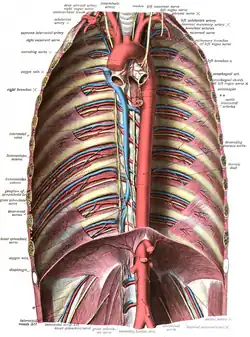

Aorta torácica

Se denomina así a la mitad de la aorta descendente que va desde el final del cayado aórtico hasta el diafragma. Diámetro promedio 2,5 cm.[10]

Aorta abdominal

Recibe este nombre la mitad de la aorta descendente que abarca desde el diafragma hasta la bifurcación de la misma. Diámetro promedio 2 cm en abdomen medio y 1,8 cm en la bifurcación.

- Ramas de la porción descendente torácica: arterias bronquiales, arterias esofágicas, ramas mediastínicas de la aorta torácica y arterias intercostales posteriores.